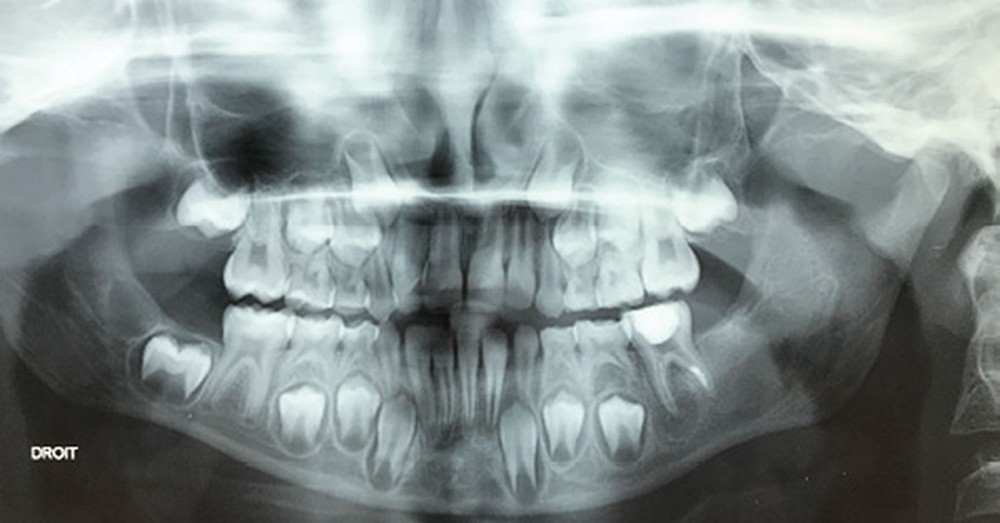

Les kystes et tumeurs bénignes osseuses maxillaires ou mandibulaires chez l’enfant sont le plus souvent asymptomatiques. Ces lésions osseuses sont découvertes de façon fortuite lors d’un bilan radiographique de routine réalisé par l’odontologiste pédiatrique ou l’orthodontiste [1-3]. Néanmoins, des lésions peuvent parfois se développer rapidement et être destructrices [1, 2]. Certains signes cliniques spécifiques à la chronologie de l’éruption dentaire chez l’enfant doivent nous alerter tels qu’un retard d’éruption dentaire ou une éruption dentaire asymétrique (fig. 1). D’autres manifestations cliniques, moins spécifiques à l’enfant, peuvent également orienter le clinicien sur la présence d’une pathologie osseuse sous-jacente : mobilité dentaire, douleur, tuméfaction, limitation de l’ouverture buccale, trouble neurosensoriel, etc. [3]. C’est la radiographie panoramique qui va ensuite mettre en évidence/confirmer la présence d’une lésion intra-osseuse (fig. 2).

La radiographie panoramique permet une première interprétation de la lésion osseuse (localisation, nombre, taille approximative, etc.). Cet examen est souvent complété par un bilan d’imagerie en trois dimensions de type Cone Beam [4]. Il précisera le volume et les limites de la lésion ainsi que ses rapports avec les structures anatomiques avoisinantes (tableau 1). Ces données radiologiques confrontées à l’examen clinique et à la fréquence relative des lésions permettent de réaliser un diagnostic d’intuition qui orientera la prise en charge.